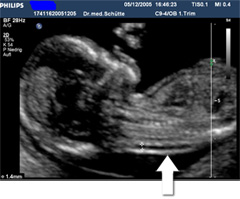

Messung der Nackentransparenz

Das zweite Bild zeigt eine auffällige

Nackentransparenz.